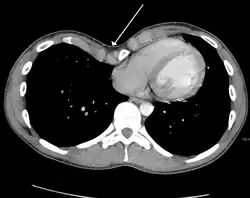

Tension pneumothorax

Tension pneumothorax is an emergent condition in which air gets trapped in the space between the chest wall and the lung. This space is referred to as the pleural space. Because air can't escape from this space, the air pocket grows larger and larger, resulting in the lung collapse closest to the pneumothorax. Forces are transmitted to the mediastinum and effectively "push" the mediastinal structures to the opposite side of the chest.[5]